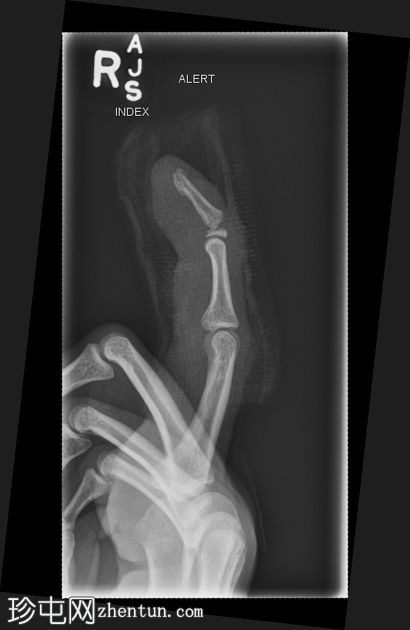

X线片

侧位片

右食指远节指骨基底部横向移位骨折,伴有背侧成角,最符合成人型Seymour骨折。指尖小骨折。

本例为罕见的成人型Seymour骨折,此类骨折通常发生于骨骼未成熟的远节指骨骨骺处。